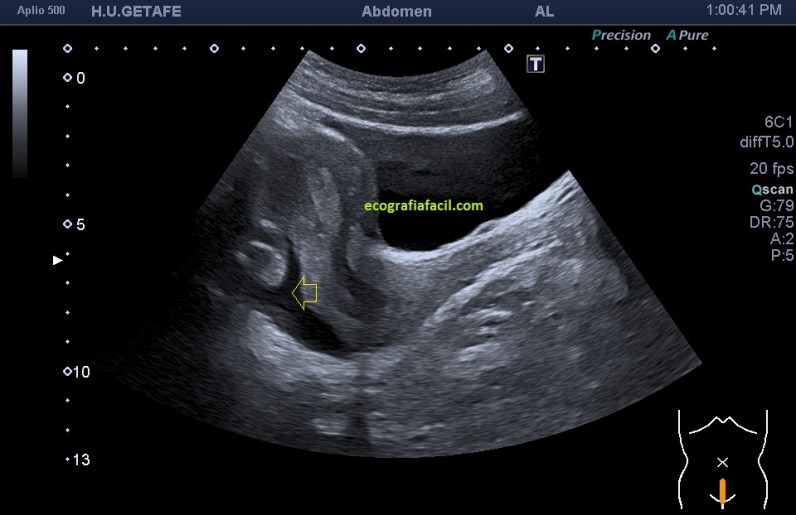

En la imagen 2, mismo corte de la imagen 1 ya me llama poderosamente la atención la cantidad de líquido que encontré en el fondo del Saco de Douglas, que puede ser normal según el periodo del ciclo en el que se encuentre la mujer, acto seguido realicé corte axial, con este resultado: